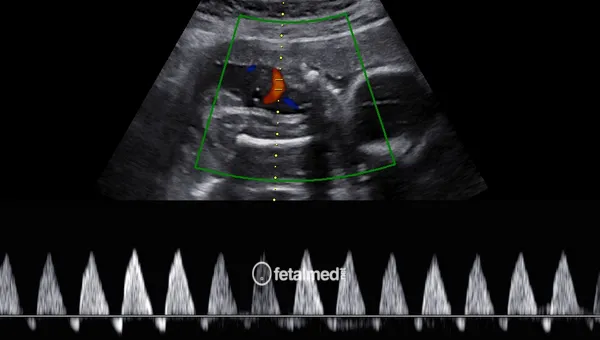

Dopplerfluxometria Obstétrica

Dopplerfluxometria obstétrica para avaliação do fluxo sanguíneo fetal e placentário. Monitoramento da vitalidade fetal em Curitiba.